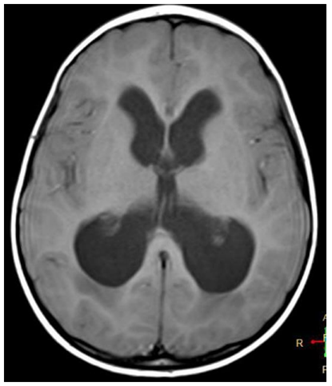

Observe o exame a seguir.

Esse exame mostra